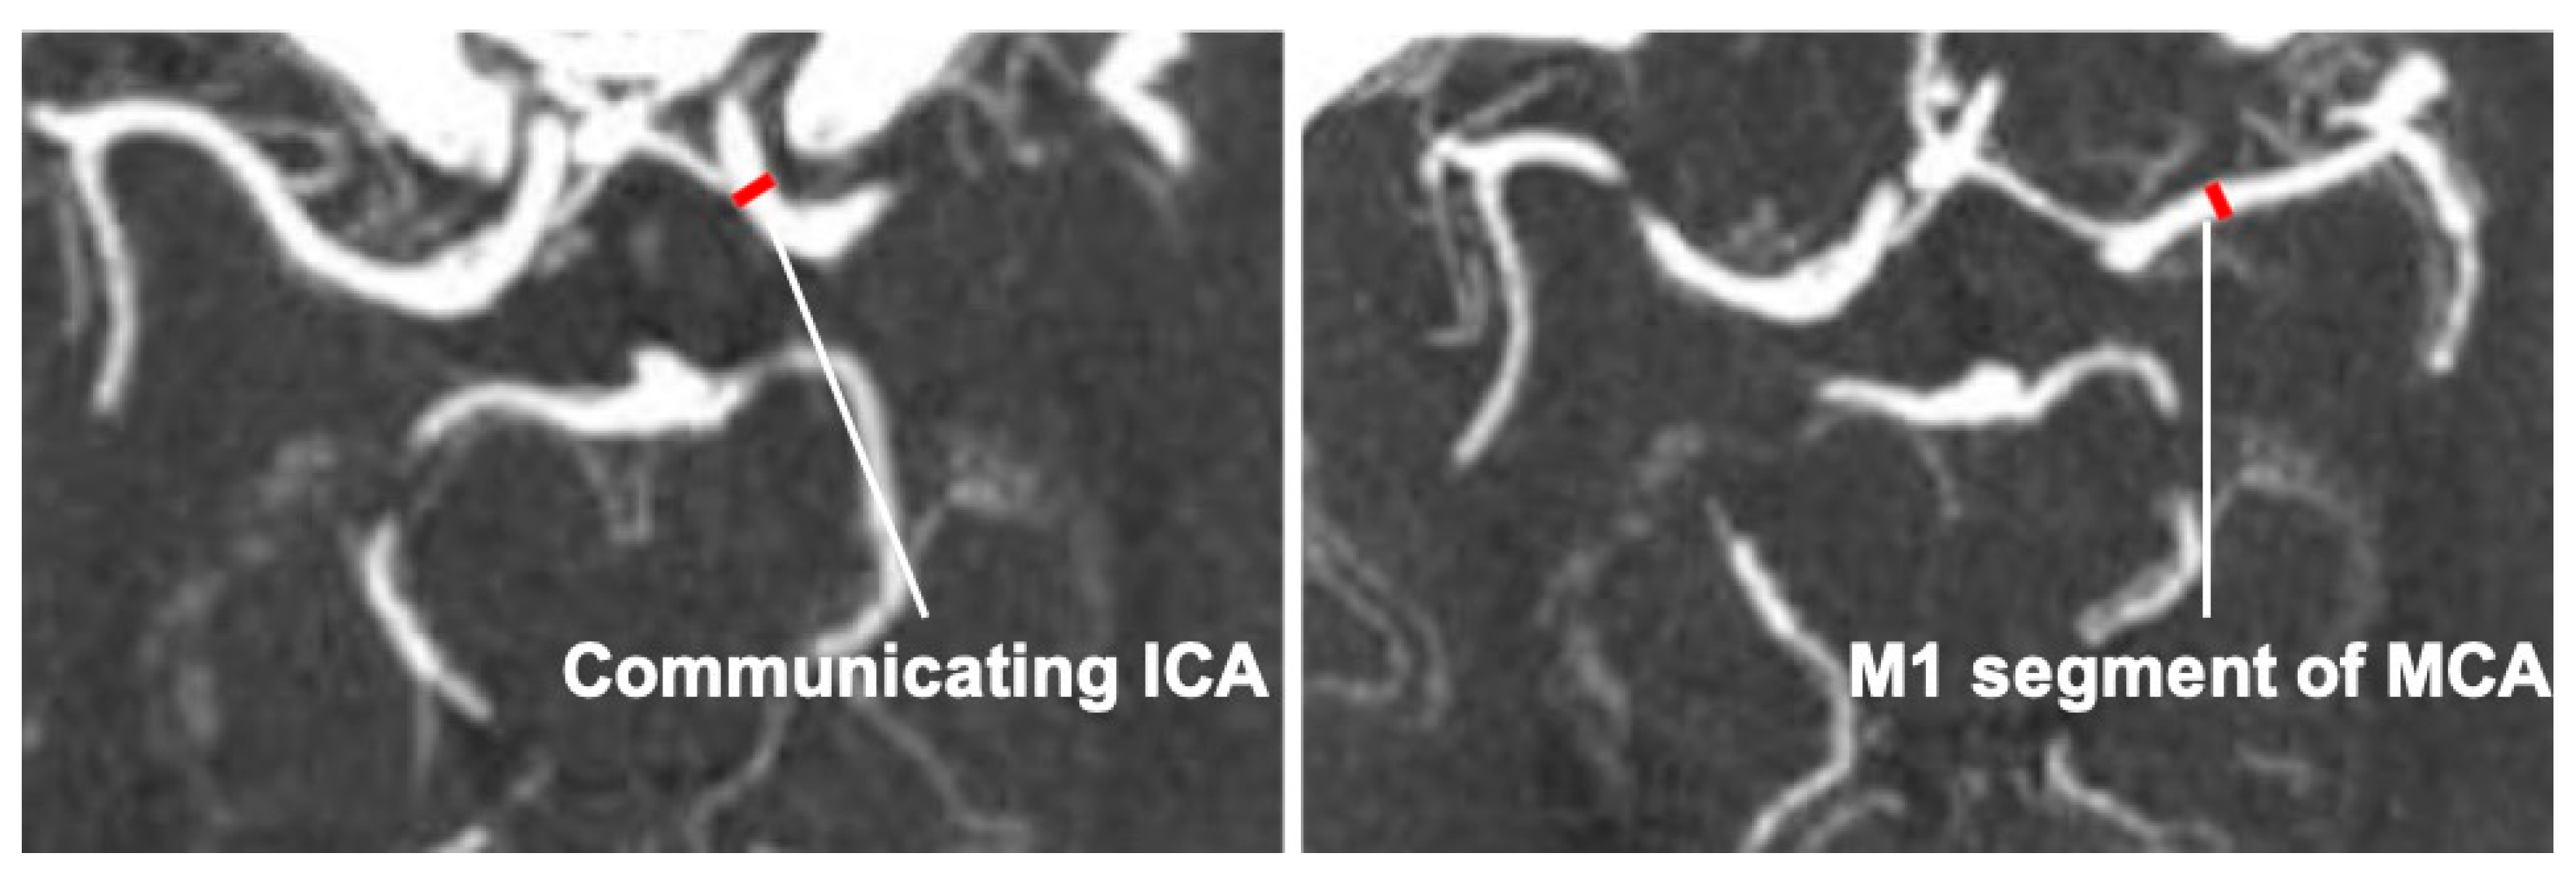

2.2. Measurements